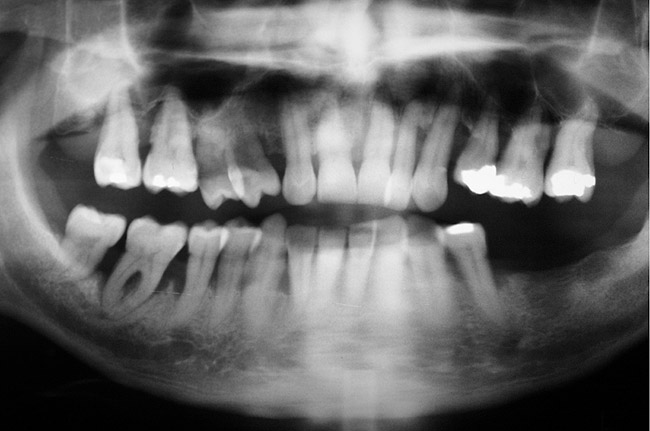

Next, the clinician must consider the teeth’s proximity to critical structures. Figure 16 shows a panoramic radiograph of a patient with advanced periodontal disease. As can be seen in this radiograph, the bone loss around the maxillary molars was very close to the maxillary sinuses and the bone loss of the distal and furcal areas of tooth No. 30 was close to the inferior alveolar nerve. This demonstrates an adverse effect of keeping teeth too long. In this case, the bone height in the area of tooth No. 19, where the tooth had been lost years earlier (and no RPD was worn), was significantly more coronal than in the area of tooth No. 30.

Figure 16  Panoramic radiograph showing generalized advanced bone loss. In the lower left quadrant, teeth Nos. 17 through 20 were lost many years earlier, and the bone level has a significantly more coronal position than the corresponding lower right quadrant where the teeth were retained.